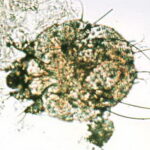

Histologic examination of a specimen containing a burrow reveals that the burrow in almost its entire length is located within the horny layer . Only the extreme, blind end of the burrow, where the female mite is situated, extends into the stratum malpighii . The mite has a rounded body and measures about 350 to 450 IJm in length and 250 to 350 IJm in width . |

Pathogenesis. Earlier scanning electron microscope studies revealed the keratinocytes around the burrow to be compacted, indicating that the mite physically forces its way in between the keratinocytes rather than chewing a passage (48). More recent studies, however, also using transmission electron microscopy, have found that the secretion of cytolytic substances by the mite as a contributing factor in advancing the parasite body through the skin in addition to mere compression (53). The cellular damage was greatest around the body, especially the mite capitulum. |